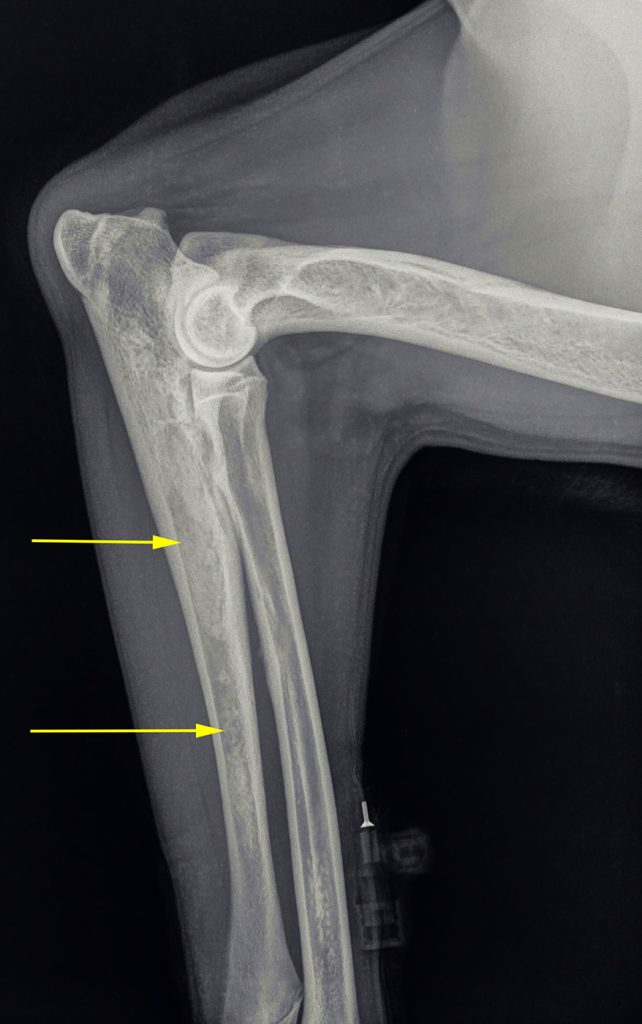

Op röntgenfoto’s kan groeipijn vaak zichtbaar gemaakt worden; het uit zich als wolkvorming in de mergholtes van de lange botten. De pijnlijkheid kan meestal met pijnstilling opgelost worden. Omdat het echter alle lange botten kan aantasten, wisselt de kreupelheid die hiermee gepaard gaat regelmatig van poot. Het kan dan ook voorkomen dat de kreupelheid in bijvoorbeeld de voorpoot overgaat, om na een maand in de achterpoot op te treden.